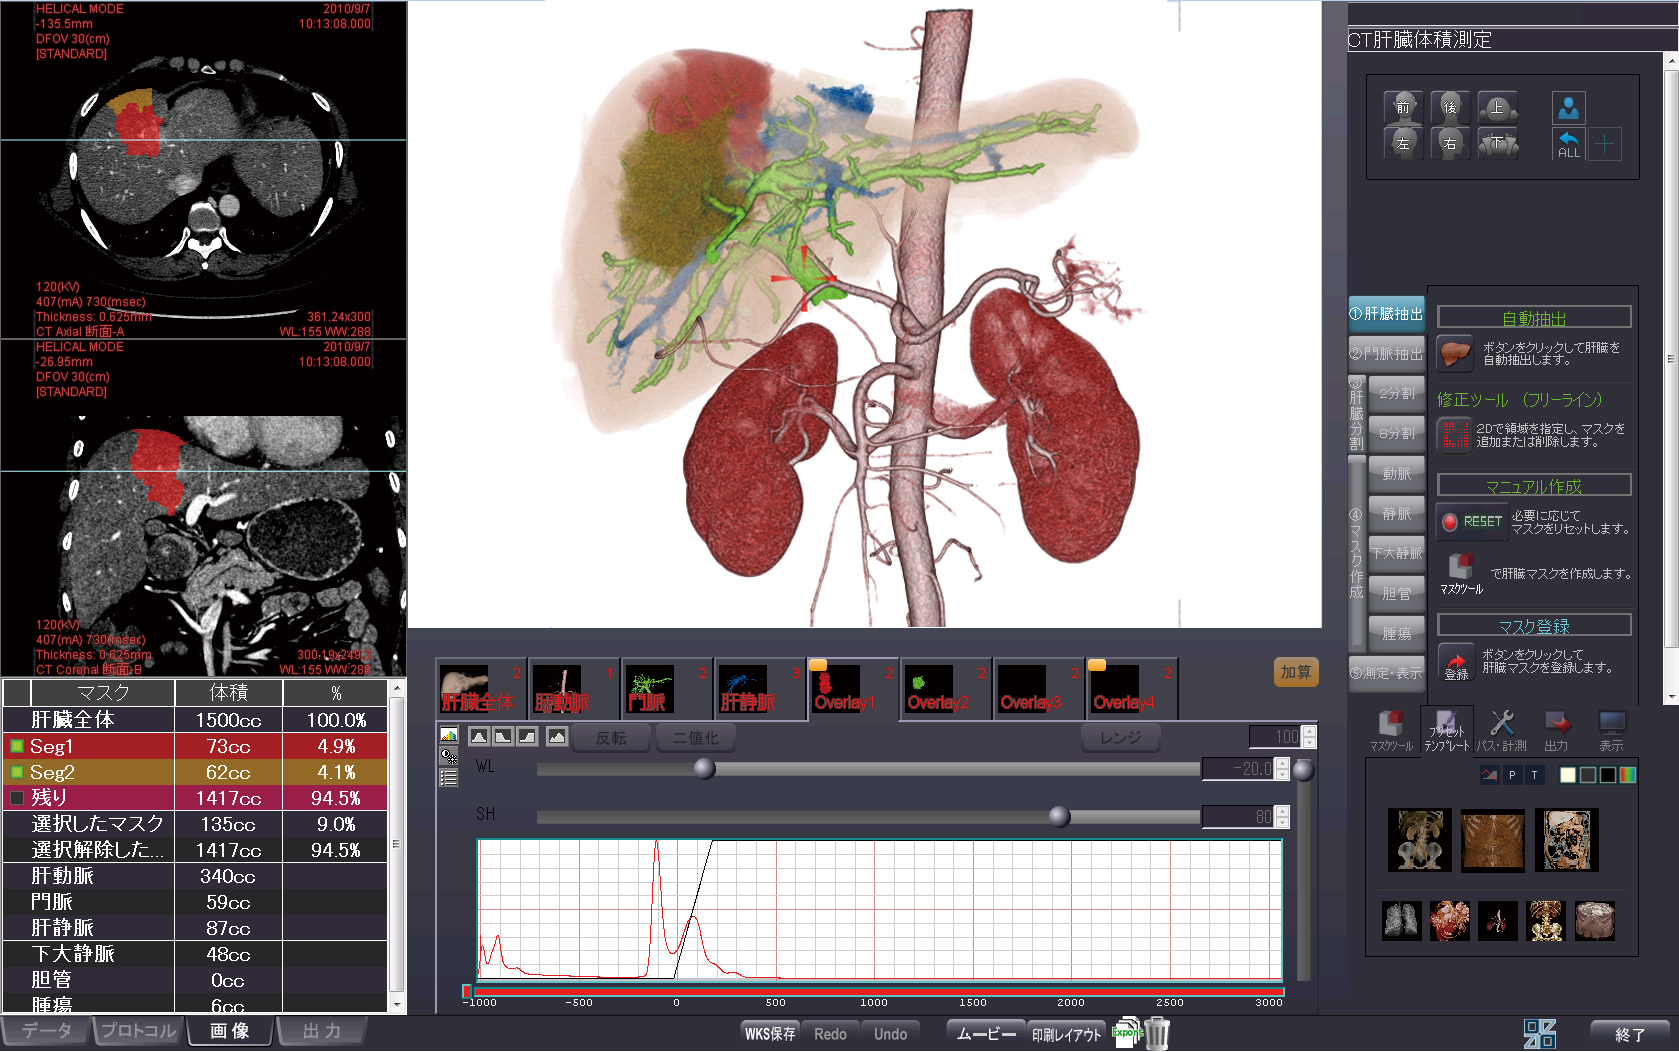

ziostation2によるCT/SPECT心臓フュージョン検査の経験は現在までで30〜40例。「やはり心臓のフュージョン画像が有用性を発揮するのは虚血領域の同定時。とりわけ境界領域、例えば右冠動脈(RCA)、左冠動脈回旋枝(LCX)、高位側壁枝(HL)、対角枝など、確定診断を下し難い領域での責任血管と虚血領域の同定がより容易になります」と泉氏は語る(図1 対角枝(#9)かHLか診断に迷う症例(HLが虚血))。

図1a:Stress

図1b:Rest

図1c:Reversibility